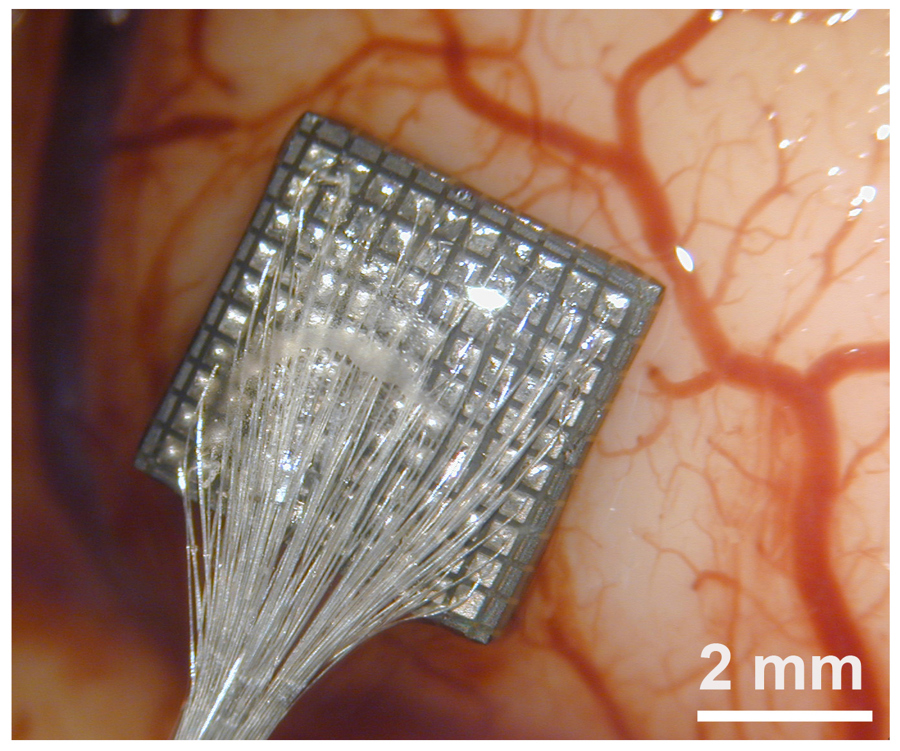

BISC es distinta: todo el implante, que ocupa menos de una milésima parte del tamaño de un dispositivo convencional, es un único chip de circuito integrado de semiconductores complementarios de óxido metálico (CMOS) con un grosor de solo 50 micrómetros, como un cabello humano.

Con un volumen total de aproximadamente 3 mm³, el chip flexible se adapta a la superficie del cerebro pero integra 65.536 electrodos, 1.024 canales de registro simultáneo y 16.384 canales de estimulación.

Para probar los métodos quirúrgicos e implantar el dispositivo de forma segura, los autores usaron modelos preclínicos y demostraron su calidad y estabilidad. Ahora se están haciendo estudios en pacientes humanos.

“Los implantes pueden insertarse a través de una incisión mínimamente invasiva en el cráneo y deslizarse directamente sobre la superficie del cerebro en el espacio subdural. Su forma delgada como el papel y la ausencia de electrodos que penetren en el cerebro o cables que unan el implante al cráneo minimizan la reactividad de los tejidos y la degradación de la señal con el tiempo”, comenta Youngerman.